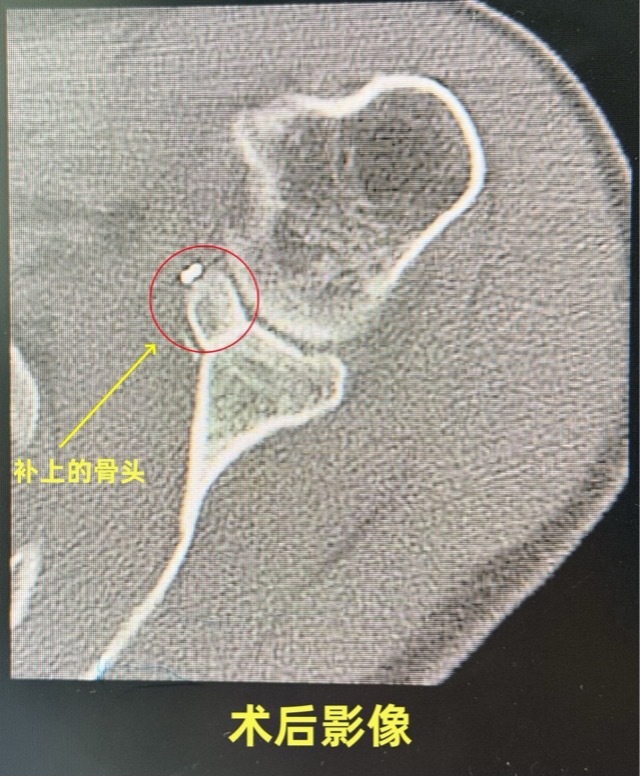

手术原理很巧妙:从肩前侧取一小块自带肌腱的“骨头支架”,移植到缺损的“底座”上,重建一道“骨头护栏”,让肩关节稳如磐石。但过程堪比在神经、血管、肌腱的“雷区”精工雕刻,每一步都考验着医生的手上功夫。

1月13日,Marc接受了手术,医生仅用不到两小时就为他解除了困扰十几年的“任性肩膀”。“我以为会疼到裂开,结果居然能睡整觉!”术后第二天,Marc就对着镜头竖起大拇指。